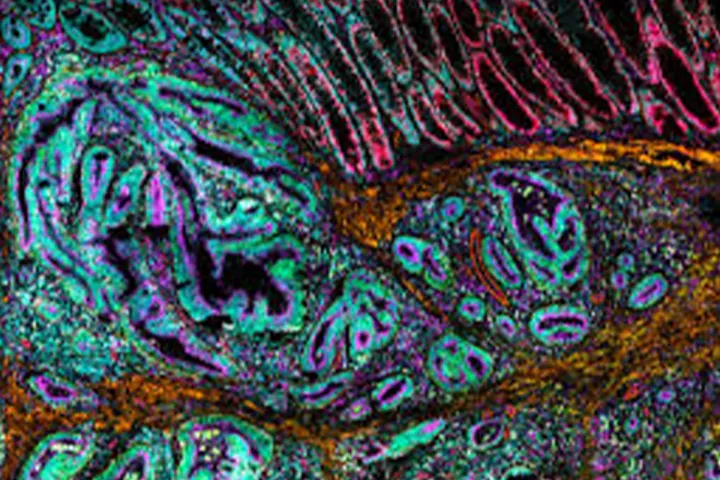

The MACSima platform offers fully automated ultra-high-content imaging based on cyclic immunofluorescence, enabling researchers to analyze hundreds of markers within a single tissue section or cell sample without damaging the specimen. This approach provides precise spatial insight into cell localization and interactions within complex tissue environments.

The system breaks the conventional limits of fluorescence multiplexing and is particularly suited for deep phenotyping applications, including immuno-oncology (tumor microenvironment mapping), neuroscience, and the study of complex infectious diseases.

Photo: Denisa Pavelková